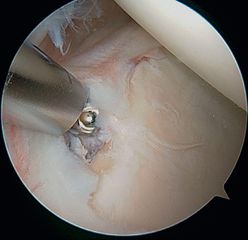

Arthroscopic SLAP II repair (right shoulder) using the posterior approach (soft point) and knotless anchors.c) Careful bone sharpening.